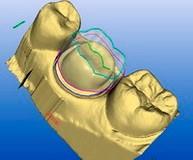

Технология изготовления. Точность технологии CAD/CAM.

CAD/CAM технология (компьютерный дизайн / компьютерно-программное изготовление) изготовления коронок на оксиде циркония принципиально отличаются от ручного литья классической металлокерамики.

Различные виды керамических блоков из оксида циркония

Коронки из оксида циркония считаются самой прогрессивной технологией современного протезирования зубов. Огромным плюсом циркониевых коронок является отсутствие металла – керамика из оксида циркония его не содержит, а целиком состоит только из фарфора. Кроме того, она намного прочнее, чем стандартная металлокерамика, которая выполняется на металлическом каркасе.Коронки из циркония обладают еще одним важным качеством, а именно - ими возможно протезировать зубы без удаления нерва за счет небольшой толщины коронки. Это позволяет минимально обтачивать зуб, тем самым предотвращая возможные воспалительные осложнения со стороны пульпы зуба.

Технология изготовления безметалловой керамики из оксида циркония включает в себя лазерное сканирование, затем производится моделирование и выпиливание (фрезерование) каркаса из цельного блока материала. Затем каркас облицовывается низкотемпературной керамикой. Такой каркас исключает раздражение десны и точно прилегает к зубу, за счет чего снижается и риск кариеса. Коронки из циркония благодаря высочайшей точности изготовления без зазоров прилегают к зубу - это важный фактор долгосрочности службы зубного протеза.

Технология изготовления. Точность технологии CAD/CAM.

CAD/CAM технология (компьютерный дизайн / компьютерно-программное изготовление) изготовления коронок на оксиде циркония принципиально отличаются от ручного литья классической металлокерамики.

Различные виды керамических блоков из оксида циркония

Коронки из оксида циркония считаются самой прогрессивной технологией современного протезирования зубов. Огромным плюсом циркониевых коронок является отсутствие металла – керамика из оксида циркония его не содержит, а целиком состоит только из фарфора. Кроме того, она намного прочнее, чем стандартная металлокерамика, которая выполняется на металлическом каркасе.Коронки из циркония обладают еще одним важным качеством, а именно - ими возможно протезировать зубы без удаления нерва за счет небольшой толщины коронки. Это позволяет минимально обтачивать зуб, тем самым предотвращая возможные воспалительные осложнения со стороны пульпы зуба.

Технология изготовления безметалловой керамики из оксида циркония включает в себя лазерное сканирование, затем производится моделирование и выпиливание (фрезерование) каркаса из цельного блока материала. Затем каркас облицовывается низкотемпературной керамикой. Такой каркас исключает раздражение десны и точно прилегает к зубу, за счет чего снижается и риск кариеса. Коронки из циркония благодаря высочайшей точности изготовления без зазоров прилегают к зубу - это важный фактор долгосрочности службы зубного протеза.